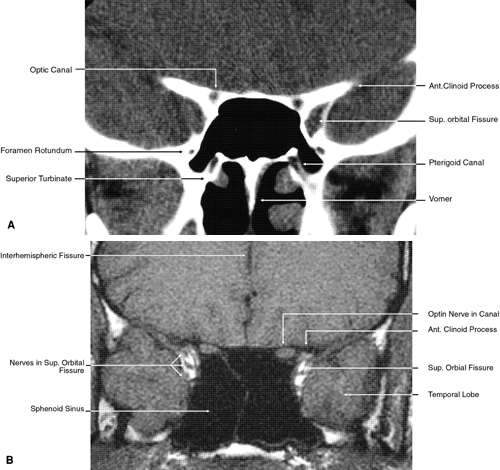

The globe is shown in Figure 12. The orbit and periorbital structures are shown in Figures 13 through 16, and the optic canal is shown in Figures 17 through 26. The cavernous sinus and optic chiasm are shown in Figures 27 and 28, and the posterior visual pathway and cranial nerves are shown in Figures 29 through 33.

Fig. 21. Coronal images through optic canal. A. Computed tomography scan. B. T1-weighted magnetic resonance imaging.

Fig. 27. Coronal images through cavernous sinus and optic chiasm. A. T1-weighted magnetic resonance imaging through anterior chiasm. B. Computed tomography image through anterior chiasm. C. Computed tomography image through posterior chiasm. D. Computed tomography image through optic tract.